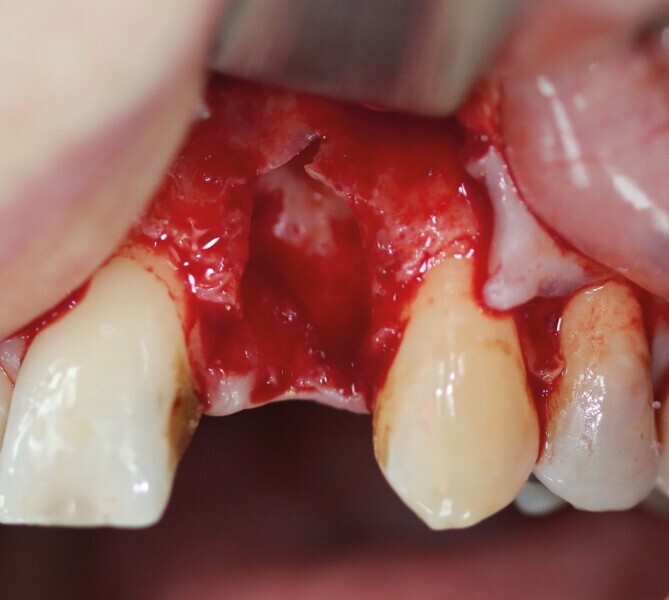

Après extraction de la première prémolaire maxillaire fracturée (Fig. 1), le soulèvement d’un lambeau a mis en évidence une perte osseuse vestibulaire sur toute la hauteur de la racine (Fig. 2). Cette lésion en « V » est rendue circulaire par un trépan de diamètre 5 mm (Fig. 3). Cela correspond au calibrage du défaut (Fig. 4). Le site d’extraction est parfaitement cureté. Le forage implantaire est réalisé contre la corticale palatine de l’alvéole d’extraction, au-delà de l’apex, pour permettre l’ancrage du futur implant. Le placement tridimensionnel de celui-ci est primordial par rapport aux collets anatomiques des dents adjacentes, ainsi que dans le sens mésio-distal et vestibulopalatin.3

Il ne faut surtout pas être piégé par la hauteur d’os perdu et enfouir plus l’implant. Un tissue level est parfaitement stabilisé grâce à ses dernières spires. (Implant TL Straumann SP 4,1 RN, longueur 12 mm SLActive). Une incision limitée en étendue et en forme de « H » est réalisée dans le secteur de la dent de sagesse inférieure, pour un abord crestal. Un trépan de diamètre supérieur au trépan de calibrage (Fig. 5), donc 6 mm dans ce cas, permet de prélever une carotte de 4 mm de profondeur (Fig. 6). Elle forme un bloc circulaire cortico-spongieux qui est impactée en force, transversalement à l’implant (Fig. 7). La surface SLActive de l’implant est au contact de l’os spongieux richement vascularisée et la partie corticale protège cet ensemble et referme parfaitement le défaut osseux (Fig. 8). L’os greffé est entouré par l’os du site receveur sur tout le pourtour. Son immobilité totale permettra sa consolidation et sa revascularisation.4 Il n’est pas utile d’enfouir l’implant ni d’utiliser une membrane, car il n’y a pas de substitut osseux (Fig. 9). La couronne définitive est réalisée à trois mois (Fig. 10). Le suivi de cette patiente montre un excellent comportement ostéo-gingival à dix ans, tant radiologiquement (Fig. 11), que cliniquement (Fig. 12).